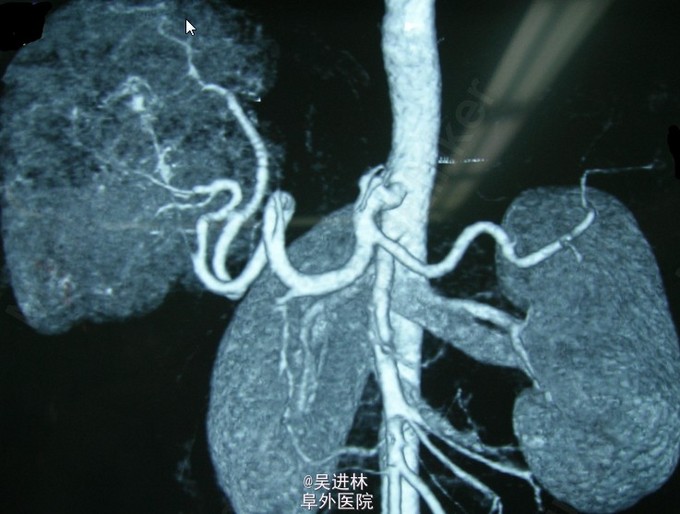

肝脏结节样增生

患者体检发现肝脏占位入院,诉肝区无明显不适,查血肝功正常。鉴于肿块较大而病人一般状况良好,考虑为良性病变,且增强扫描动脉期明显强化,故考虑为此病。肝脏局灶性结节性增生(FNH)是肝脏一种少见的良性病变,是仅次于肝血管瘤的肝脏良性肿瘤之一,病因不明。